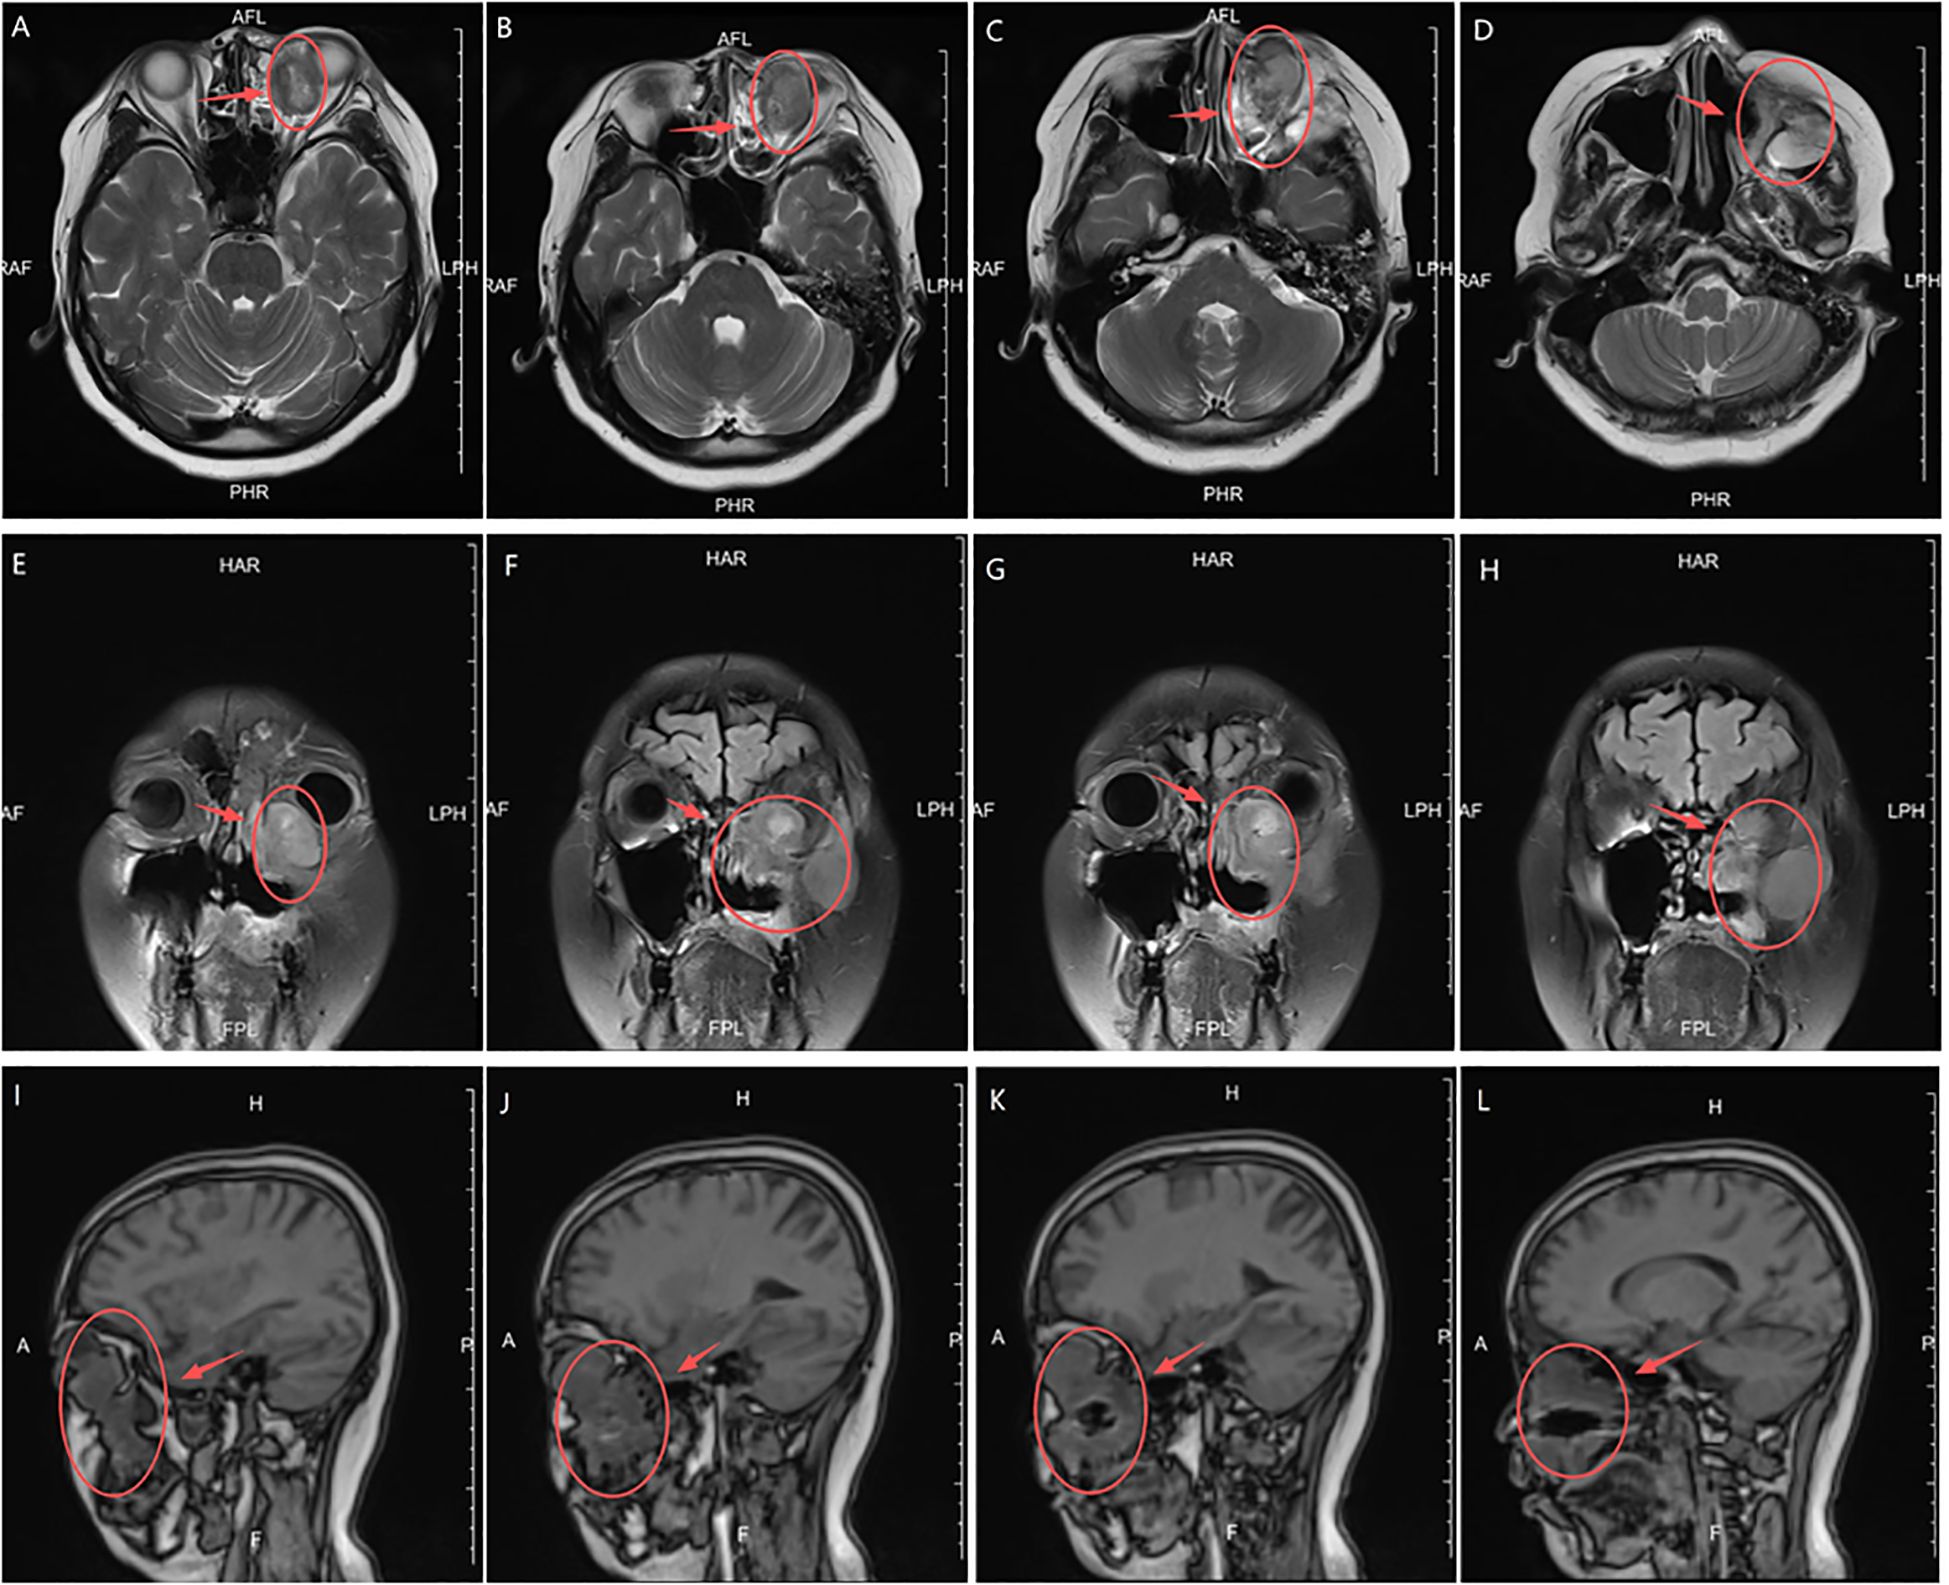

In February 2024, the patient presented with recurrent symptoms including left facial swelling, left orbital displacement, diplopia, progressive visual acuity deterioration, and ocular distension. MRI revealed local tumor recurrence, demonstrating superior growth through the superior wall of the maxillary sinus into the orbital cavity, with optic nerve compression and orbital bone destruction (Figure 1). CT findings suggest tumor recurrence. (Figure 2).

Figure 1. MRI Anatomical imaging: Findings consistent with (LGMFS) tumor recurrence involving the orbit, (as indicated by the arrows). (A–D) Axial T2-weighted image. (E–H) Coronal Short Tau Inversion Recovery (STIR) sequence image. (I–L) Sagittal T1-weighted image.